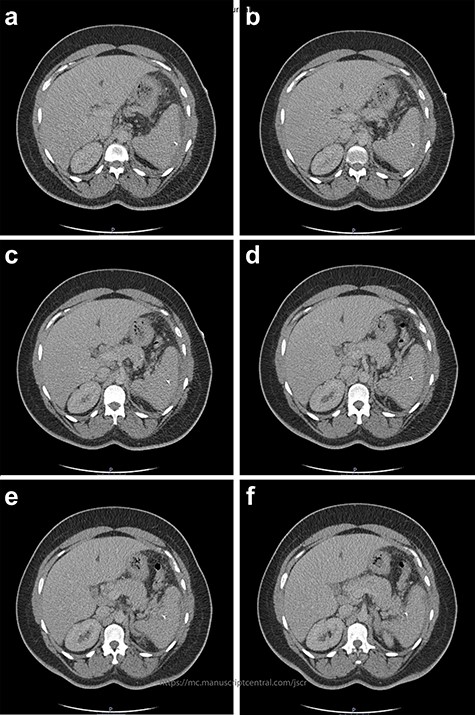

The initial bloods showed haemoglobin 121 g/l, white cell count 29.2x109/l, lactate 0.8 mmol/l, C-reactive protein 348 mmol/l and deranged alkaline phosphatase at 175 mmol/l, with other blood results in normal ranges. A diagnosis of intra-abdominal sepsis secondary to acute cholecystitis was suspected and initial resuscitation was commenced. A computerized tomography (CT) scan of the thorax, abdomen and pelvis demonstrated a mild left pleural effusion with bibasal subsegmental consolidation, splenic subcapsular haematoma, splenic hypodensity and a linear hyperdensity density crossing the upper anterior pole of the spleen, referred to hereafter as the foreign body (Figs 1–3).

Two-mm axial sections from a CT scan demonstrating the linear hyperdensity traversing the spleen across multiple cross sections. (a) Section number 65 (b) section number 67 (c) section number 69 (d) section number 71 (e) section number 73 (f) section number 75.